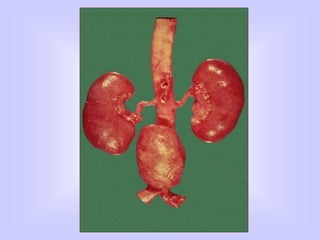

COMPLICATED ATHEROSCLEROSIS

CALCIFICATION

ULCERATION

FOCAL RUPTURE ( Atheroemboli )

HEMORRHAGE

SUPERIMPOSED THROMBOSIS

ANEURYSMAL DILATION

COMPLICATIONS

Acute occlusion

Chronic narrowing of vessel lumen

Aneurysm formation

Embolism

COMPLICATED ATHEROSCLEROSIS CALCIFICATION ULCERATION FOCAL RUPTURE( Atheroemboli ) HEMORRHAGE SUPERIMPOSED THROMBOSIS ANEURYSMAL DILATION

COMPLICATIONS Acute occlusion Chronic narrowingof vessel lumen Aneurysm formation Embolism